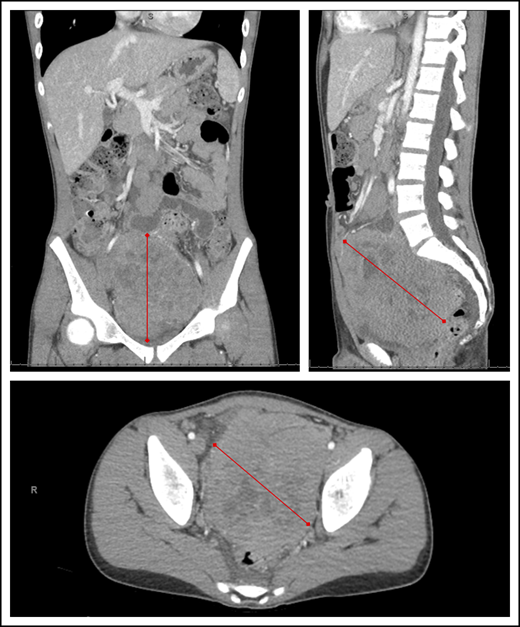

Current standards of BL treatment in SSA are still primarily based on the successes of pioneering trials from the 1970s with cyclophosphamide as the backbone agent, without differentiation of staging or risk group.25,27,36-41 Survival rates have plateaued over the past 40 years, and efforts to improve have stalled since then. Contemporary efforts to improve outcomes within the cyclophosphamide-based paradigm have included the addition of various low doses of MTX,42-44 vincristine,45 doxorubicin, and prednisone.17,20,46,47 The collective experience has demonstrated cohort survival rates ranging from 30% to 50%, with mortality primarily attributed to tumor progression or recurrence (Table 1). Patients with stage I/II BL have achieved survival of 40% to 60%, whereas survival for stage III/IV BL (typically involving the abdominal cavity, bone marrow, or CNS) has remained <30%.26,38,40,41,48-50 This is particularly relevant because numerous studies in SSA have demonstrated that abdominal mass has become at least as common as jaw mass as a presenting feature of endemic BL (Figure 1).17,20,51,52

Abdominal computed tomography imaging demonstrating a large heterogeneous mass centered within the pelvis and lower abdomen in a child with BL. Red lines represent the extent of the lymphoma mass from its outer edges.